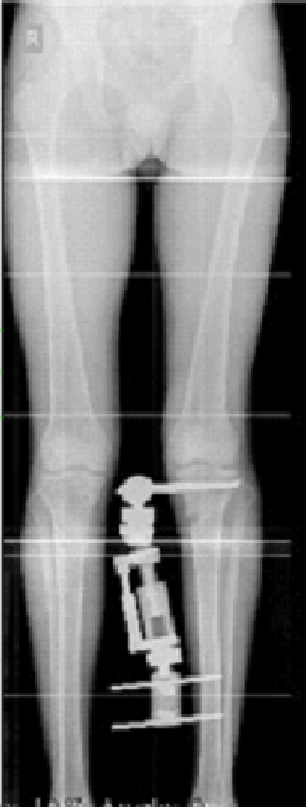

Dr.Jijeesh Dr.Jijeesh HTO is a surgical procedure used to correct the Tibial varus deformity. It is done in genu varus or bowleg. Bowleg is a condition in which the legs have a gradual or sudden bent due to various reasons. The term varus means bent inwards and the term valgus means bent outward Normally, on standing both the knees bear equal weight. And in the knee the weight distribution is more on medial or inner side than outer side. So any increase in small degree of varus will cause more force on the medial side than lateral side. In case of valgus small degree wont have much effect on the lateral side. When a person has bowlegs there is increased load on the inner side of the knee more commonly (Varus) or the outer side of the knee (Valgus). This increased loading causes that side to wear out faster and then presents as pain. Generally the body is able to compensate slight bow in the legs by the action of muscles. But when the bent is beyond a certain limit then the muscles cannot compensate and this results in reduction in the joint space and gradual worsening of the angle. When the cartilage of the joint wears out it is called reduced joint space or arthritis knee, which is due to overload. These arthritic changes are called secondary osteoarthritis Ie, arthritis due to bend or some secondary cause. Whereas primary osteoarthritis is the term used in case of wear and tear of knee joint due to old So, in these type of arthritis ie arthritis due to varus otherwise known as medial compartment osteoarthritis the treatment is to correct the alignment of the knee by doing a surgery called High Tibial Osteotomy. HTO is indicated not in all patients with genu Varus. Occasional pain that settles with rest doesn’t require surgery immediately. Generally, in about 80-90% people this settles down with proper exercises and medication for a few days. But if there is worsening on the x-rays even without much pain, then there is a role of correction of the deformity as a “preventive surgery”.

By changing the angle of bone the bow is corrected and the load-bearing axis or the mechanical axis of the limb is brought back to the center of the knee joint. This shift helps in taking the load off the affected side and relieves the pain, but more importantly it helps the overloaded side to get rest and heal. As the healing progresses the narrowed joint space again fills up cartilage. In HTO the principle is to cut the Tibia through a small incision (about 1.5 cm) few inches below the knee; an external fixator is applied to the bone; the angle is then gradually corrected by turning a nut on the fixator (1 mm per day) to a pre-defined point and the fixator is then locked. The fixator remains for a total of 3 months, because that is the time for the bone to heal and become solid. Once the bone healed the Fixator can be removed as an OPD procedure. And there is no. need of any second surgery. The second method is HTO using plate. Here instead of orhofix fixator plate is used for fixation of bone. The advantage is, there is no implant outside the body. But the disadvantage is to get a perfect alignment on standing weight bearing in all cases.